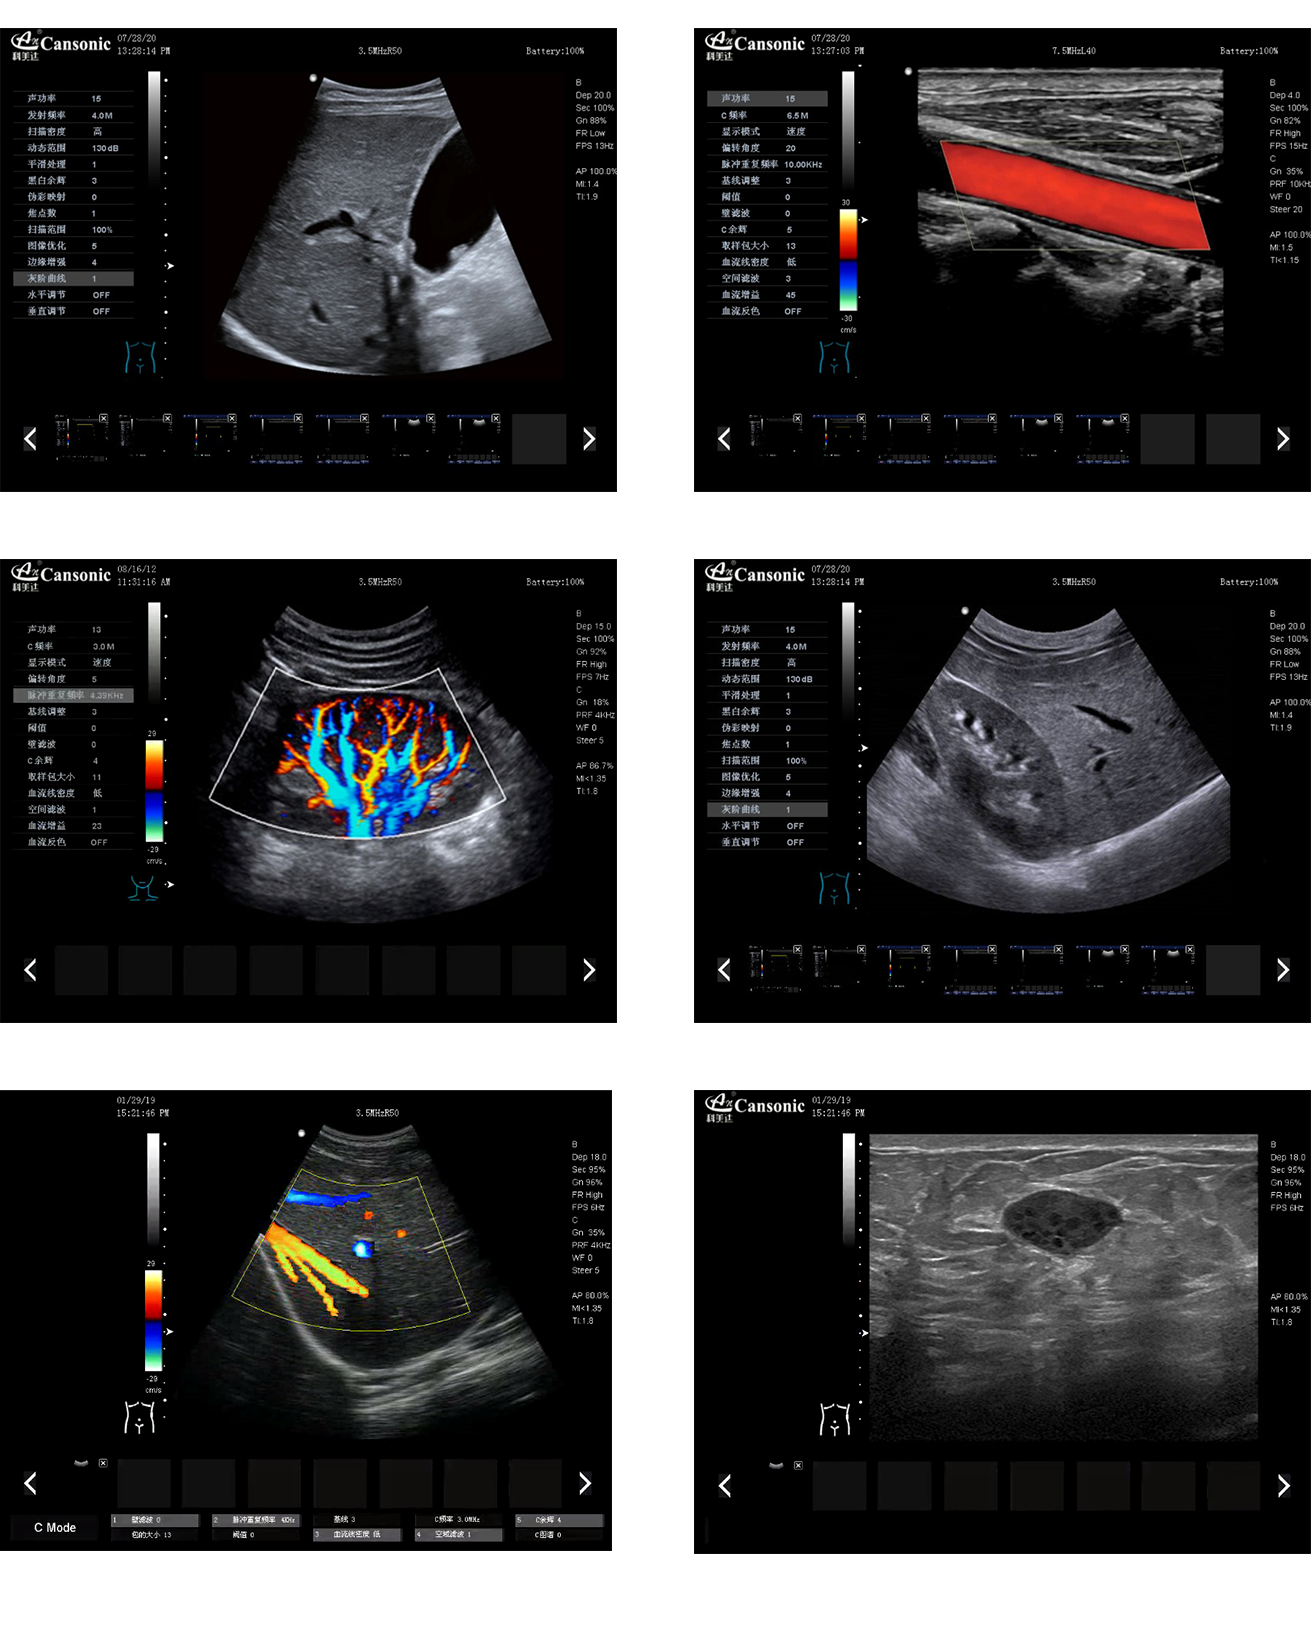

科美達K8圖像實例

1、全新一代便攜彩超,采用高端彩超技術,提供完整的臨床解決方案,適應各種臨床環(huán)境

2、圖像細膩,質量優(yōu)異,同時性能穩(wěn)定,每天能做大量檢查

3、選擇手動或自動包絡頻譜,一鍵顯示各種血流動力學數據

4、高分辨率灰階血流成像,明顯提升對微細血管的血流探測能力,對大血管管壁成像及管壁斑塊的診斷有著很大幫助